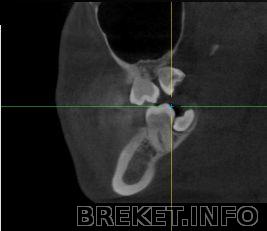

панорамный снимок